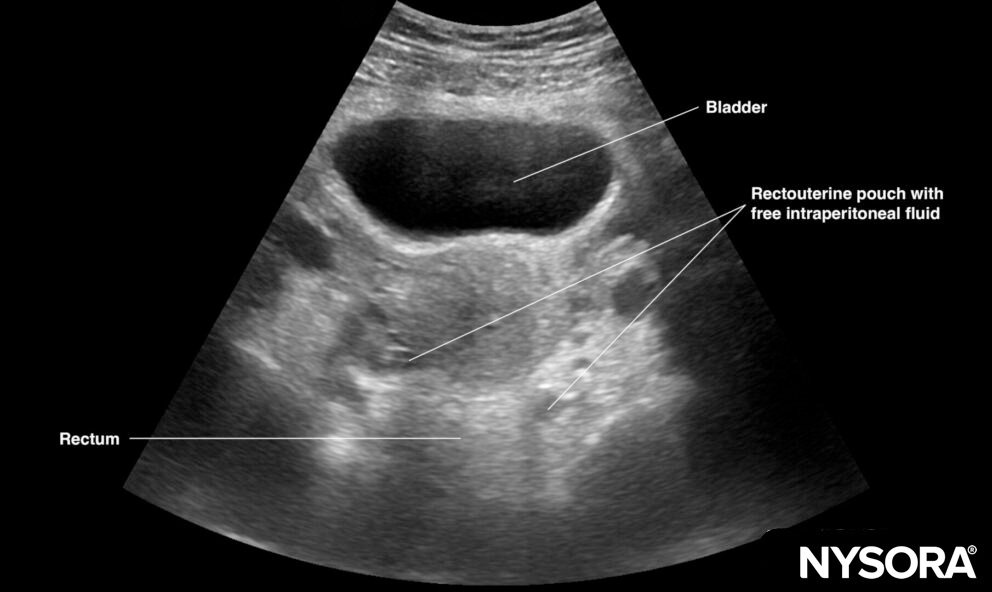

Sonoanatomy of interest in females:

Longitudinal view of the female pelvis with free fluid in the rectouterine pouch.

Pelvic free fluid collects behind the bladder or the area lateral to the bladder (rectovesical pouch in men and the rectouterine pouch or pouch of Douglas in women).

Sagittal section through the pelvis with free fluid in the rectovesical pouch in men and the rectouterine pouch (pouch of Douglas) in women.